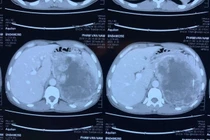

(khoahocdoisong.vn) - Nhờ sự chuyển giao kỹ thuật từ Bệnh viện Việt Đức và Bệnh viện Bình Dân, khoa Ngoại Tiết niệu - Bệnh viện Đa khoa tỉnh Thanh Hóa đã thực hiện rất nhiều kỹ thuật cao, kỹ thuật chuyên sâu chuyên ngành Tiết niệu và Nam học, cứu sống nhiều người bệnh. Một người bệnh có khối u tuyến thượng thận khổng lồ vừa được phẫu thuật thành công nhờ chuyên môn cao và thiết bị hiện đại.

(khoahocdoisong.vn) - U tuyến thượng thận là bệnh dễ gây tai biến, dẫn đến tử vong. Bé 19 tháng tuổi không sốt, bụng to dần do mang trong mình khối u tuyến thượng thận kích thước lớn đẩy nhu mô gan và thận phải xuống dưới... đã được phẫu thuật thành công tại Bệnh viện Sản Nhi Quảng Ninh.

U tuyến thượng thận (UTTT) là bệnh nguy hiểm không chỉ gây ảnh hưởng tới sức khoẻ, tinh thần mà còn khiến chất lượng cuộc sống giảm nghiêm trọng, dễ biến chứng tử vong. Nhờ sự chuyển giao kỹ thuật từ Bệnh viện Hữu nghị Việt Đức, Bệnh viện Đa khoa Thanh Hóa đã làm chủ kỹ thuật này, mổ cho bệnh nhân an toàn, nhanh hồi phục